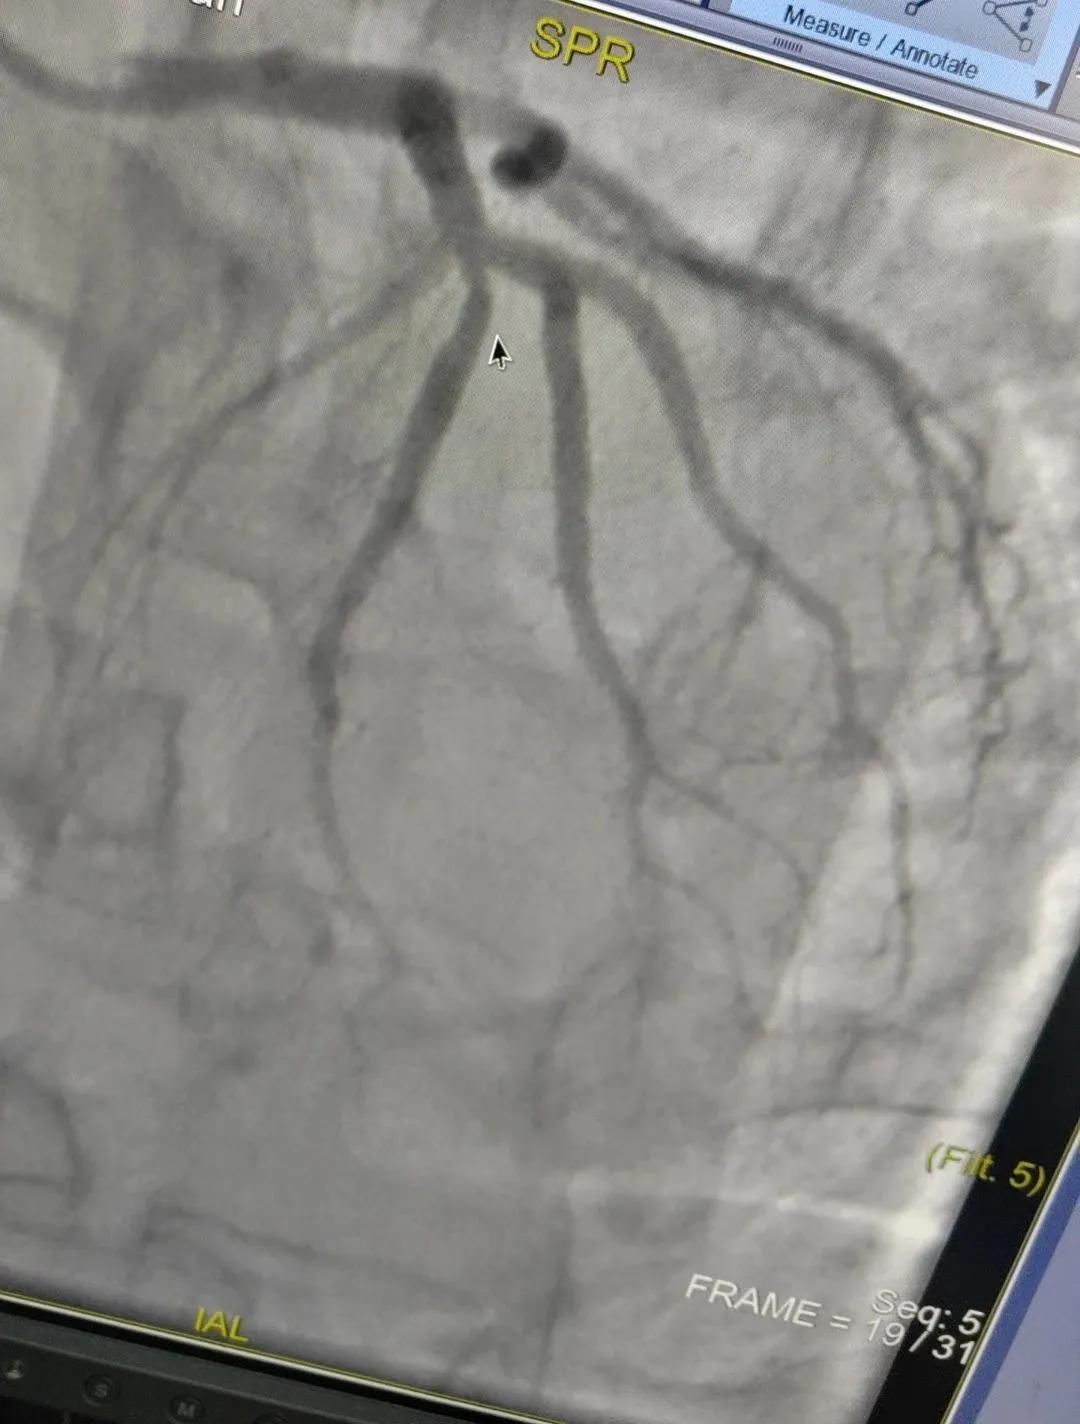

術(shù)中心血管造影顯示:LAD中段發(fā)出D1處可見(jiàn)約50%節(jié)段性狹窄,RCA中段狹窄約40%,PLA可見(jiàn)約70%狹窄病變。

腦血管造影顯示:左側(cè)頸內(nèi)動(dòng)脈嚴(yán)重遷曲,左側(cè)大腦前動(dòng)脈未顯影,左側(cè)大腦中動(dòng)脈M1中段以遠(yuǎn)未顯影,M1近段串珠樣嚴(yán)重狹窄,顱底可見(jiàn)少量煙霧血管,后交通動(dòng)脈未開(kāi)放;右側(cè)頸內(nèi)動(dòng)脈嚴(yán)重遷曲。右側(cè)大腦前動(dòng)脈A1段嚴(yán)重遷曲。